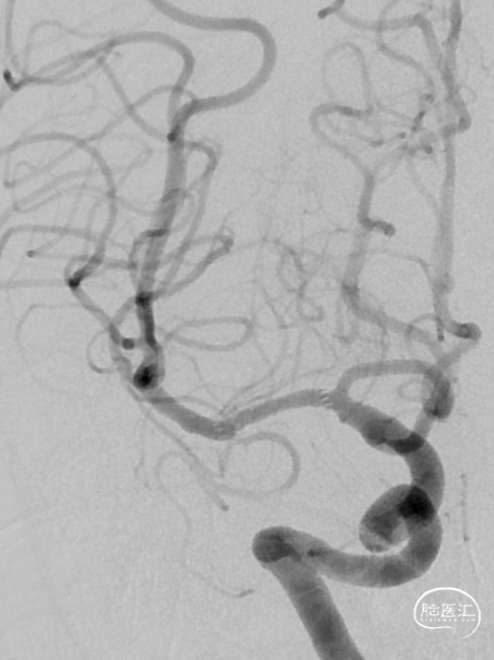

术前造影:

造影显示RICA:C1段起始部闭塞,残端呈锥形,TICI分级0级;RMCA未显影,远端由RACA经皮层支少量代偿,ASITN分级1-2级。

将Catalyst7 132中间导管经导引导管送至于RICA C1段起始部闭塞处,采用ADAPT技术自C1段至C4段反复抽吸取栓,取出大量暗红色血栓。

手推冒烟见RICA C1-C5段显影,C5段以远闭塞。将Pro-18微导管在Synchro(0.014×200mm)微导丝引导下送至RMCA M2段,微导管冒烟示远端血流通畅。将Trevo XP(4×20mm)取栓支架于M1段远端向RICA末端释放,采用SWIM技术取栓1次,并同时将中间导管送至颈内动脉末端抽吸。抽出数枚暗红色血栓。

造影见RICA再通,RMCA M1段近端重度狭窄,约90%。